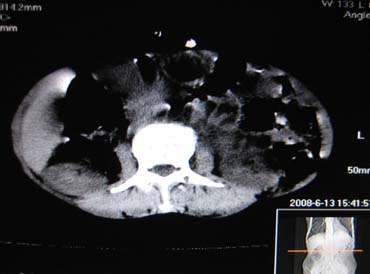

女,65岁,左上腹痛。

肝脏占位  脾脏及胰腺病变   请提供病史

肝脾胃左肾胰都显示不正常啊

病史不详,肝、脾、胰都有占位,谁是原发?

淋巴瘤及肝癌(转移瘤?)可不可以不用一元论解释呢。

胰腺癌伴脾脏侵犯并肝内转移可能性大  建议增强扫描  否则没有确凿的依据

考虑姨尾癌,腹膜后转移\\肝转移

没有病史,没有强化,那就只有猜了,我看病灶很像肝、脾及腹腔多发脓肿,这只是我的意见,

图像欠清,病灶与胃脾胰肾上腺关系显示欠清,建议增强,肝脏考虑转移瘤.

多脏器占位,腹膜后淋巴结增大,淋巴瘤?建议增强扫描